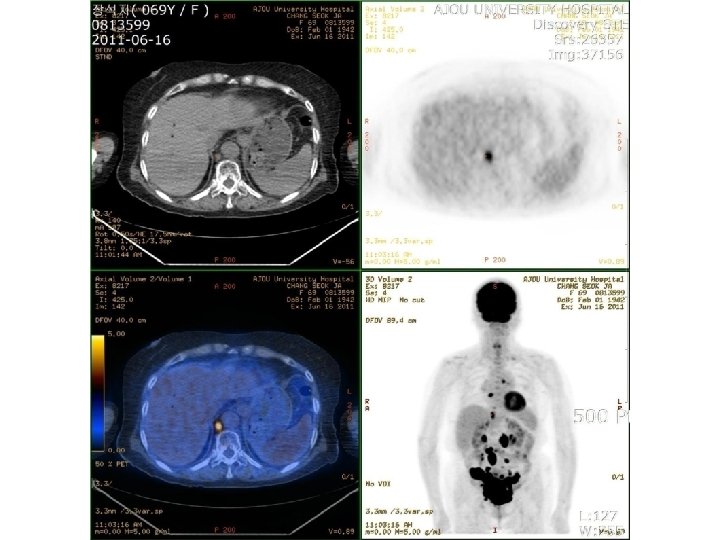

Discussion • Less than 1% of extranodal lymphomas arise from gynecologic tract. 7~30% of secondary involvement. • 23~30% sensitivity of conventional Pap smear • More challenging on liquid preparations

Hyperchromatic cells with high N/C ratio on Pap smear 1. Long list of differential

Hyperchromatic cells with high N/C ratio on Pap smear 1. Long list of differential diagnosis benign/reactive, preneoplastic, and neoplastic process 2. Careful systematic evaluation of squamous and glandular elements as well as the background component 3. Correlation with clinical history and radiological findings